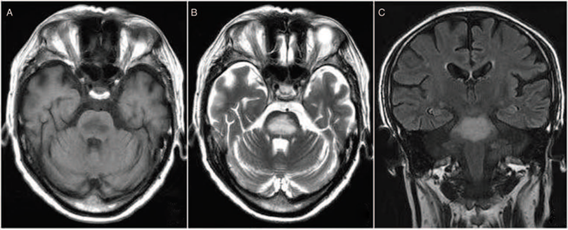

影像表现(MRI):特征性表现为第三四脑室旁及导水管周围、乳头体、四叠体、丘脑等部位对称性长 T1 长 T2 异常信号影,T2-FLAIR 呈高信号,急性期可有强化。有些少见部位如小脑齿状核、桥脑被盖、红核、中脑顶盖、尾状核及大脑皮质也可见类似影像学改变,MRI 表现为病变部位对称性 T2WI 高信号影。

二、Marchiafava-Bignami病(Marchiafava-Bignami disease, MBD)

此病又称原发性胼胝体变性,是一种与慢性酒精中毒相关的罕见疾病,以胼胝体脱髓鞘和坏死为主要病理特征。临床上可分为急性、亚急性和慢性三种类型。急性起病者可迅速出现意识障碍、癫痫发作等严重症状;亚急性及慢性者多表现为言语障碍、肌张力增高、痴呆等。慢性型常出现大脑半球连接功能障碍(分离综合征)。

影像表现:急性期后胼胝体异常信号逐渐消退。慢性期表现为胼胝体萎缩伴局灶性长T1、T2信号,可能反映了进行性脱髓鞘、局灶性坏死和囊变。MBD患者也可出现胼胝体外受累,以皮质下白质最为多见,其他部位包括小脑中脚、内囊、前联合以及皮层。